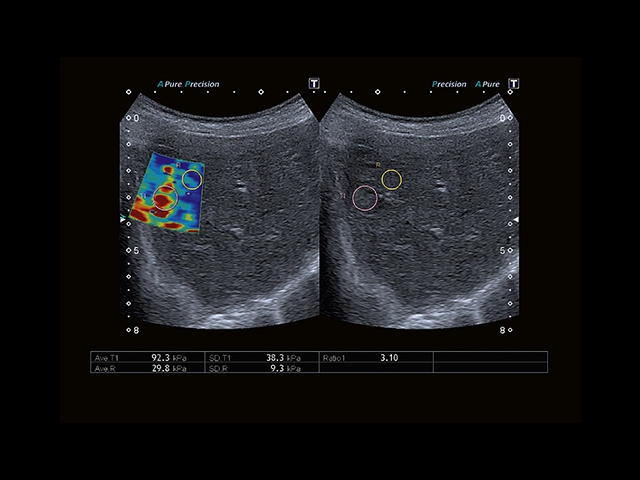

Обновленная версия легендарного УЗ-сканера. Стационарный аппарат экспертного класса Aplio 500 Toshiba NEW, визуализирует анатомические структуры в высоком разрешении. Модель позволяет выявить микрокальцификаты, новообразования, нарушения в работе сердца, сосудов и мышц. Присутствует функция виртуальной эндоскопии, 4D-сканирования, эластометрии тканей, УЗИ с контрастированием. За повышение качества изображения отвечают технологии ApliPure и Superb Microvascular Imaging. Первая задействует возможности пространственного и частотного кодирования, формирует цельный визуальный ряд с сохранением клинических маркеров. Вторая улучшает отображение микрососудистого русла, используя доплеровский эффект. Модель оснащена 21-дюймовым монитором, имеет 4 активных порта. Возможно подключение педиатрических, интраоперационных, лапароскопических и чреспищеводных датчиков.

Компрессионная

Эластография сдвиговой волной/Эластометрия:

Компрессионная эластография: